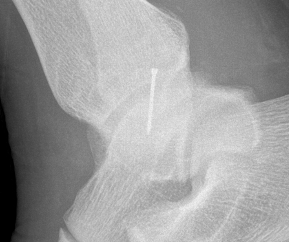

Xray

Stage II medial osteochondral fragments

Stage III medial osteochondral fragments

Stage IV anterolateral osteochondral fragment